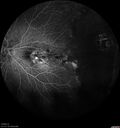

18 year old female - She was born at term. She had a goopy teardrop. She was told that she had toxoplasmosis in the left eye and that had harmed the vision. The right eye is OK. She has been getting yearly retina checks. They wanted to get a second opinion on the two eyes. She did have laser in the left eye in 2016 for a tear.  No family history of eye disease.

VA OD: Dcc20/25 NccJ1

VA OS: Dcc20/200+1 Ncc20/400

IOP: TP: OD:17 OS:14

Anterior segment normal – clear lenses

Familial Exudative Vitreoretinopathy - FEVR - Stage 1-b both eyes288 viewsShe was born at term.   No family history of eye disease.